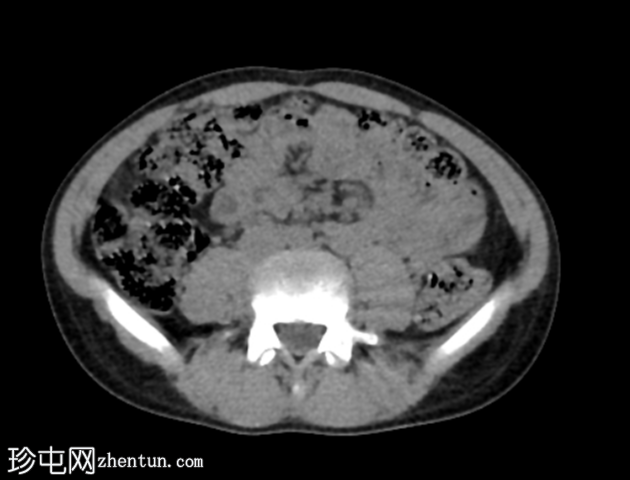

轴位

平扫

腹部和盆腔CT扫描结果正常。

泌尿系统正常。未见尿路结石或反流压改变。

本病例显示一名10岁男孩的腹部、盆腔和泌尿系统CT扫描结果正常。